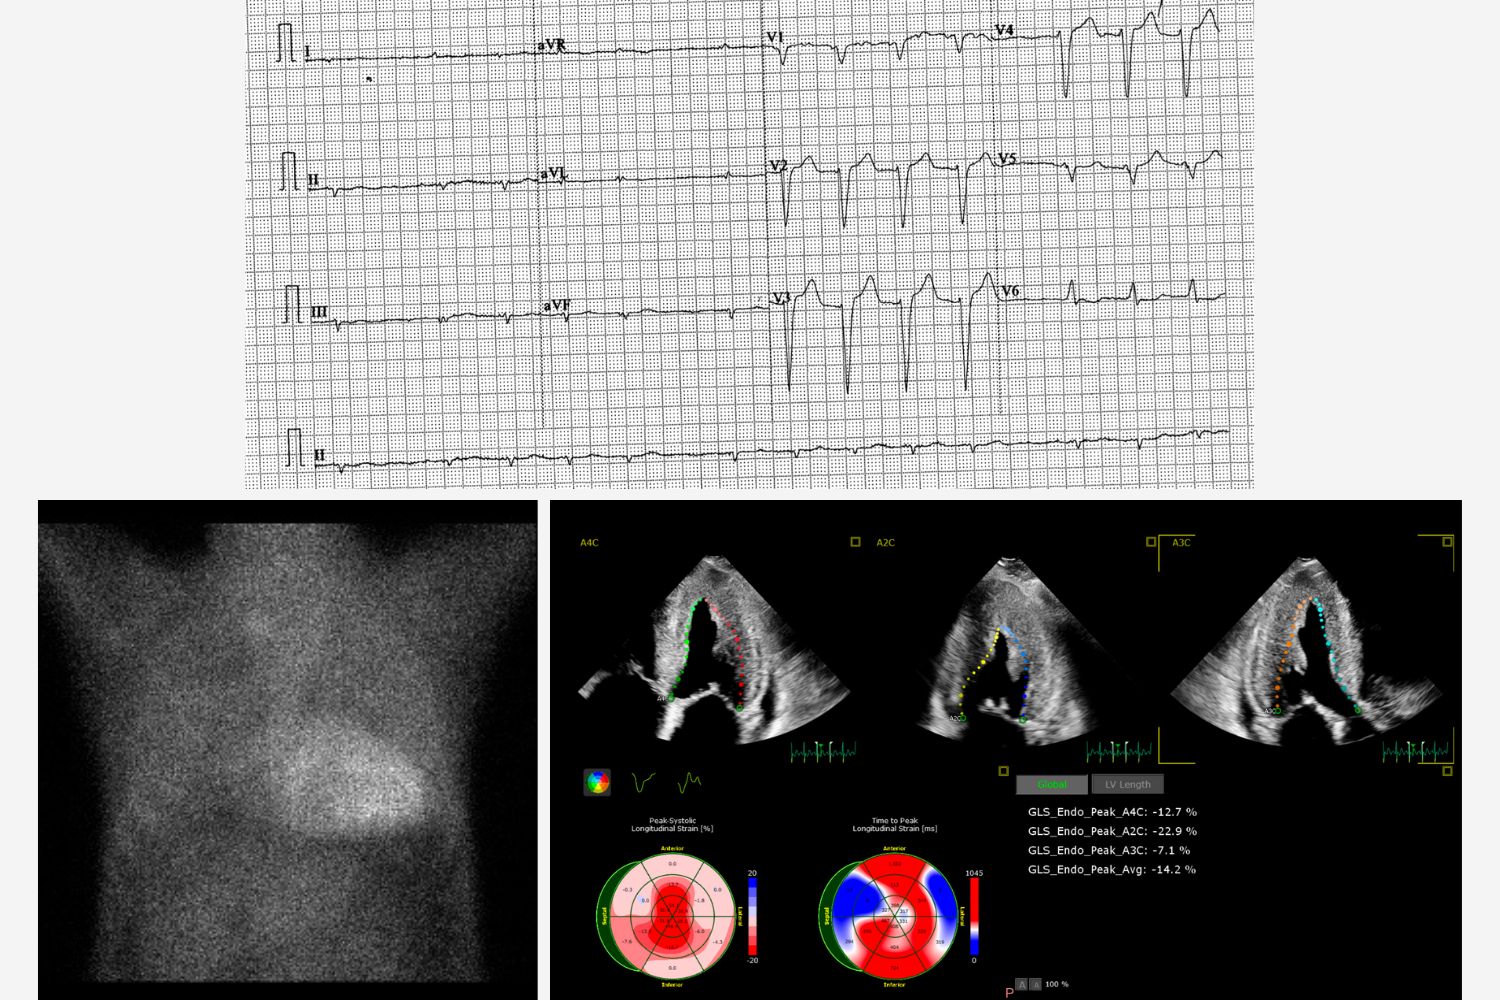

Image of the Week - 22 October 2025

Doctor Nur Rahma Almaraz

Doctor Elena Sufrate Sorzano

Miss Teresa Gonzalo Moreno